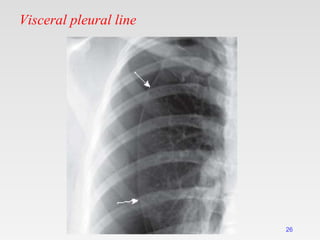

Visceral pleural line

26

DD of visceral pleural line

Skin fold:

• Positive mash band (optical edge enhancement).

• Extend beyond the chest wall.

• Lung markings extend beyond it.

Scapular edge